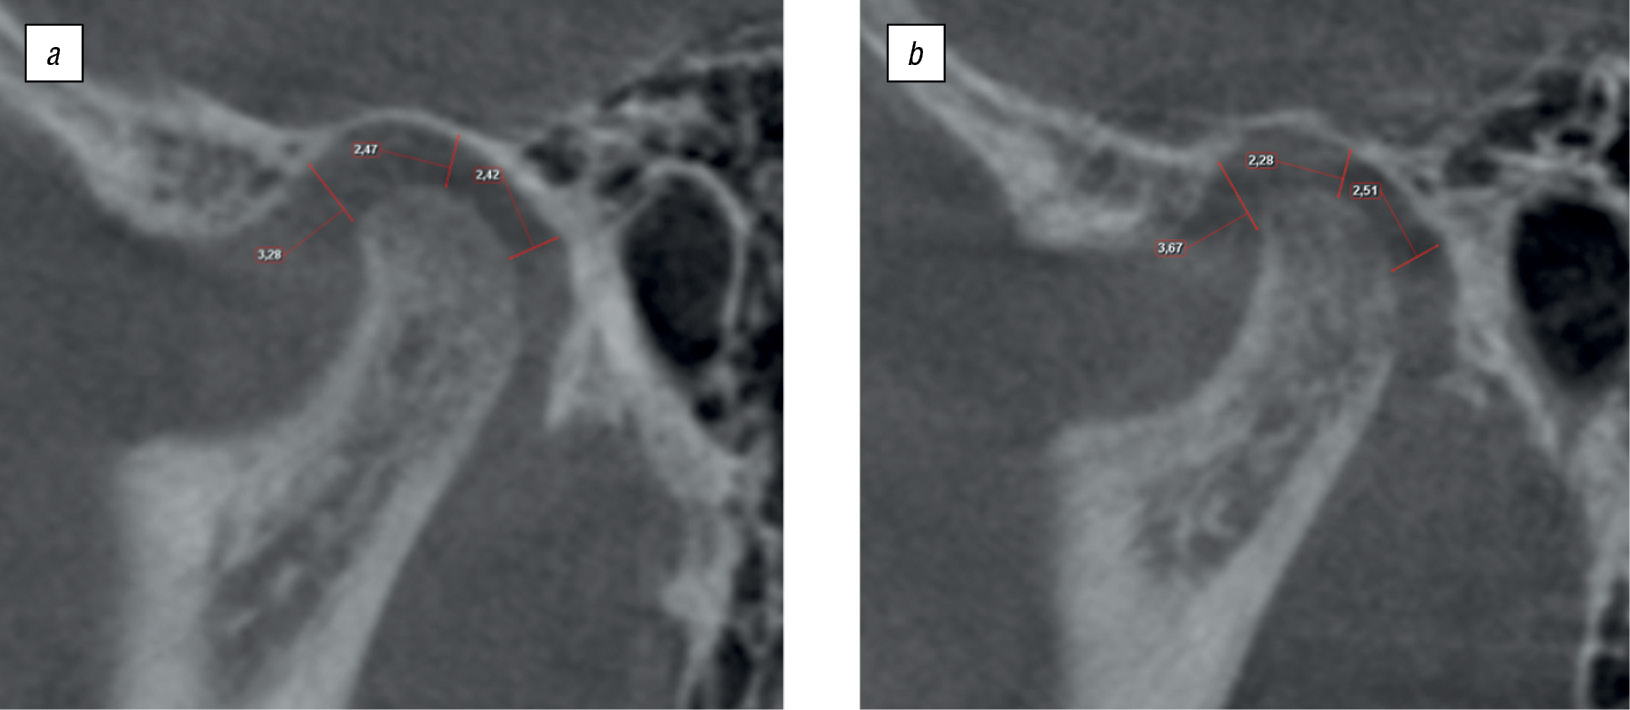

Результаты измерения размера суставной щели ВНЧС по методике Н.А. Рабухиной (рис. 6) представлены в табл. 1.

Рис. 6. Анализ томограмм височно-нижнечелюстного сустава по Н.А. Рабухиной пациента П., 15 лет: a — при закрытом рте справа; b — при закрытом рте слева / Fig. 6. Analysis of the temporomandibular joint tomograms according to N.A. Rabukhina, patient P., 15 years old: a — with the closed mouth on the right; b — with the closed mouth on the left

Таблица 1. Результаты измерения суставной щели височно-нижнечелюстного сустава по методике Н.А. Рабухиной / Table 1. Measurement results: the size of temporomandibular joint space according to the method of N.A. Rabukhina

Параметр | Правый височно-нижнечелюстной сустав | Левый височно-нижнечелюстной сустав |

Ширина переднего отдела суставной щели, мм | 3,20 | 3,67 |

Ширина среднего отдела суставной щели, мм | 2,47 | 2,20 |

Ширина заднего отдела суставной щели, мм | 2,42 | 2,51 |

По данным КЛКТ в заднем отделе обнаружено сужение суставной щели справа и слева. В положении привычной окклюзии головки нижней челюсти смещены дистально. При открытом рте суставные головки располагаются на вершине суставных бугорков, что соответствует норме. Анализ угловых параметров, проведенный в программе «Краниометрия», показал отклонения в соотношении костных элементов ВНЧС. Для правого ВНЧС угол α — 8,2°, угол β — 7,688°, угол γ — 164,11°; для левого — 4,399°, 4,127°, 171,47° соответственно. Также была выявлена асимметрия в расположении суставных элементов между правым и левым ВНЧС (рис. 7).